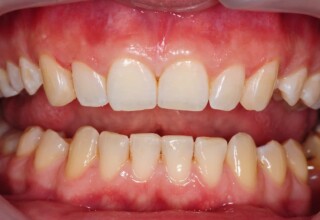

Αποκατάσταση διαστημάτων μεταξύ κεντρικών και πλαγίων τομέων

Τα διαστήματα έχουν δημιουργηθεί κυρίως λόγω των στενών πλαγίων. Μετά την ολοκλήρωση της ορθοδοντικής θεραπείας τα διαστήματα “έκλεισαν” με την τοποθέτηση δύο αποκαταστάσεων σύνθετης ρητίνης.